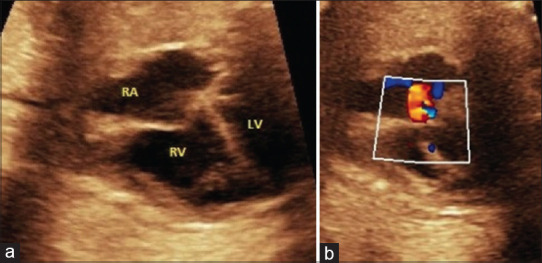

Fetal ductal constriction: An ominous but treatable entity!

胎儿导管收缩:一个不祥但可治疗的实体!